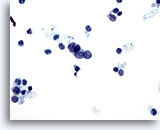

画像 1

肺FNA、単純ヘルペスウイルス肺感染症

多核化、核の相互圧排、スリガラス様クロマチンのほか、好酸性の核内封入体などウイルス性細胞変性に特徴的な様相が認められます。

60倍

画像 1

肺FNA、単純ヘルペスウイルス肺感染症

多核化、核の相互圧排、スリガラス様クロマチンのほか、好酸性の核内封入体などウイルス性細胞変性に特徴的な様相が認められます。

60倍